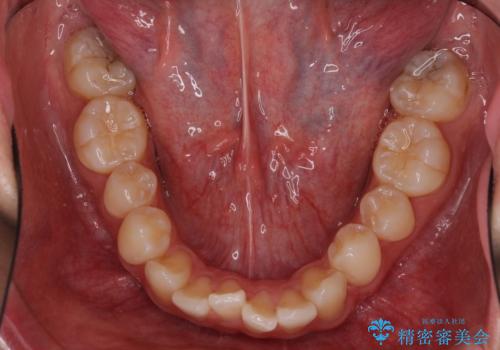

- 全体的なデコボコと、前歯の前に出ている感じを気にして来院された患者様です。

患者様と相談の上、非抜歯にてインビザラインを用いて矯正治療を行うこととし、IPR(歯と歯の間)並びに歯列全体の後方移動により口元の突出感の改善することとしました。

お仕事が忙しい方で、装着時間が不足したり、定期的な通院ができなかったりと、自己管理が重要なインビザラインによる矯正治療が長期化する要因が重なり、5年ほどの期間を要しました。